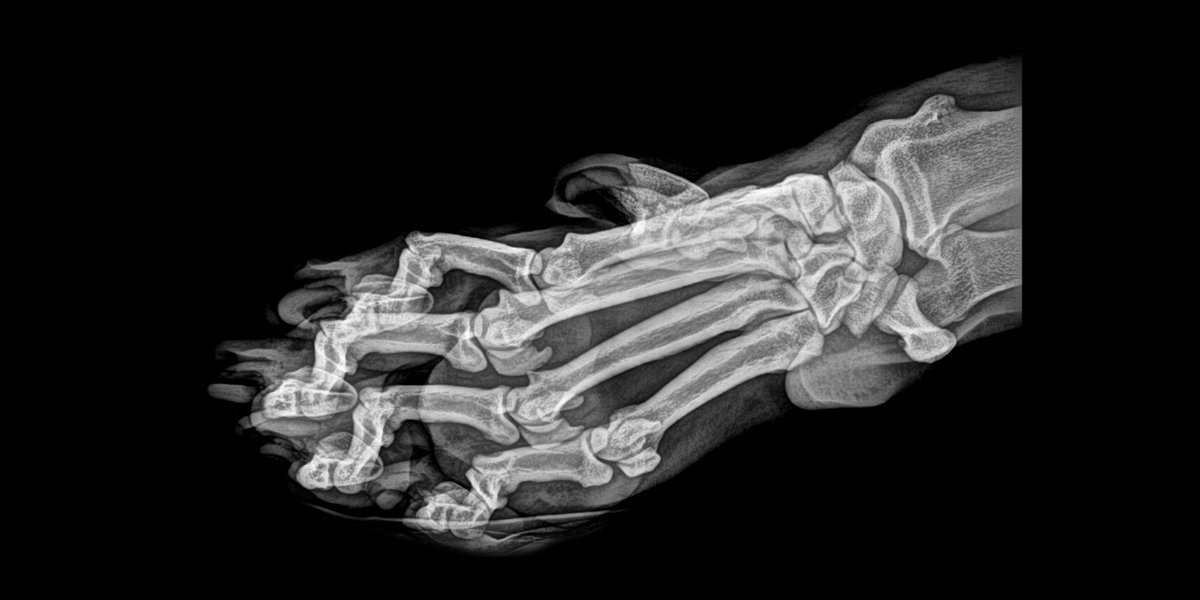

Garra de tigre